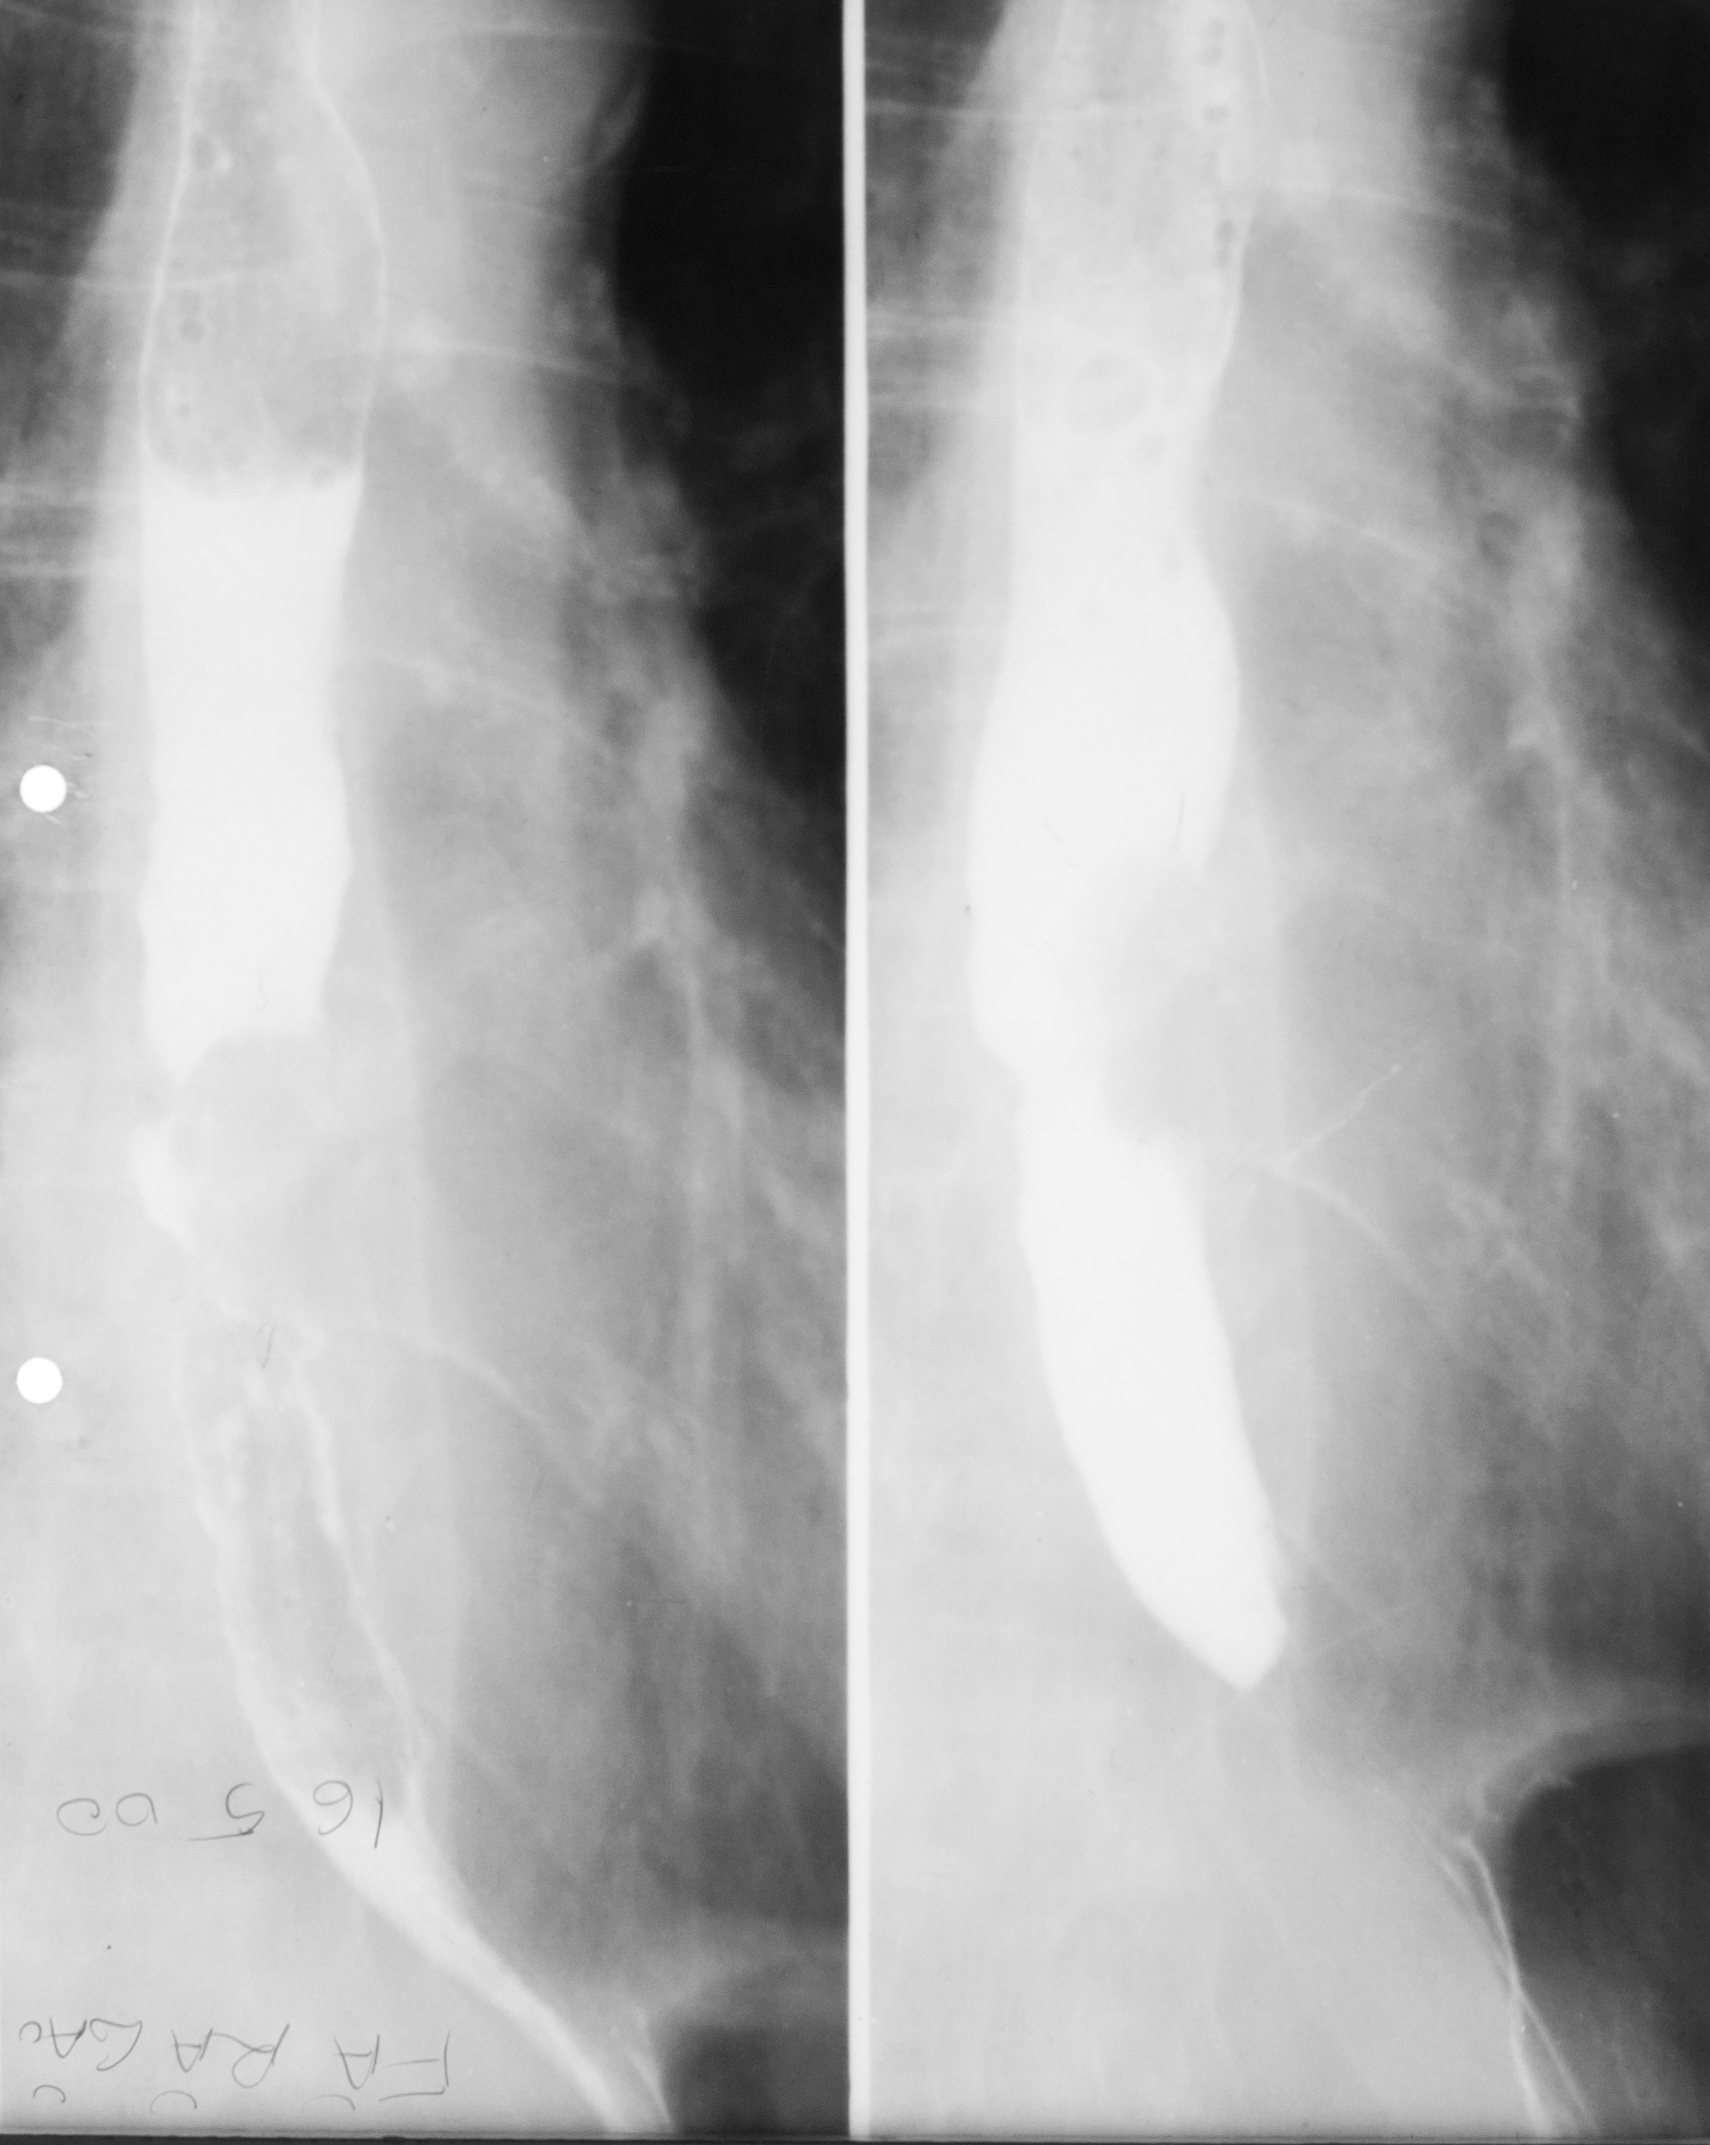

DIVERTICUL ESOFAGIAN

Tranzit baritat pe regiunea toracală

Se observă esofagul plus o imagine adiacentă a acestuia cu un camp de umplere,cu nivel orizontal și hipertransparență deasupra.

DIVERTICUL ESOFAGIAN

Tranzit baritat la nivelul esofagului.

Se observă o imagine de adiție(iese din conturul organului)

DIVERTICUL ZENKER

Tranzit baritat a esofagului pe radiografie de profil.

Se observă esofagul din profil,coloana vertebrală,imaginea de adiție cu substanță de contrast în interior și aer antidecliv

DIVERTICUL ZENKER( Văzut din față)

Pată persistentă de substanță de contrast,văzută din față,în proiecția mediastinului superior

STENOZĂ DE TIP BENIGN

Tranzit baritat la nivelul esofagului

Se observă o stenozare pe distanță mare,axială,simetrică a esofagului=Stenoză de tip benign.Se observă și o mica ulcerație:imagine de adiție triunghiulară la nivelul extremității superioare

STENOZĂ DE TIP MALIGN

Stenoză excentrică cu contur neregulat,pe o distanță mai mică

STENOZĂ DE TIP MALIGN

Contur neregulat,anfractous cu retrodilatare

Stenoză excentrică,nu este axială